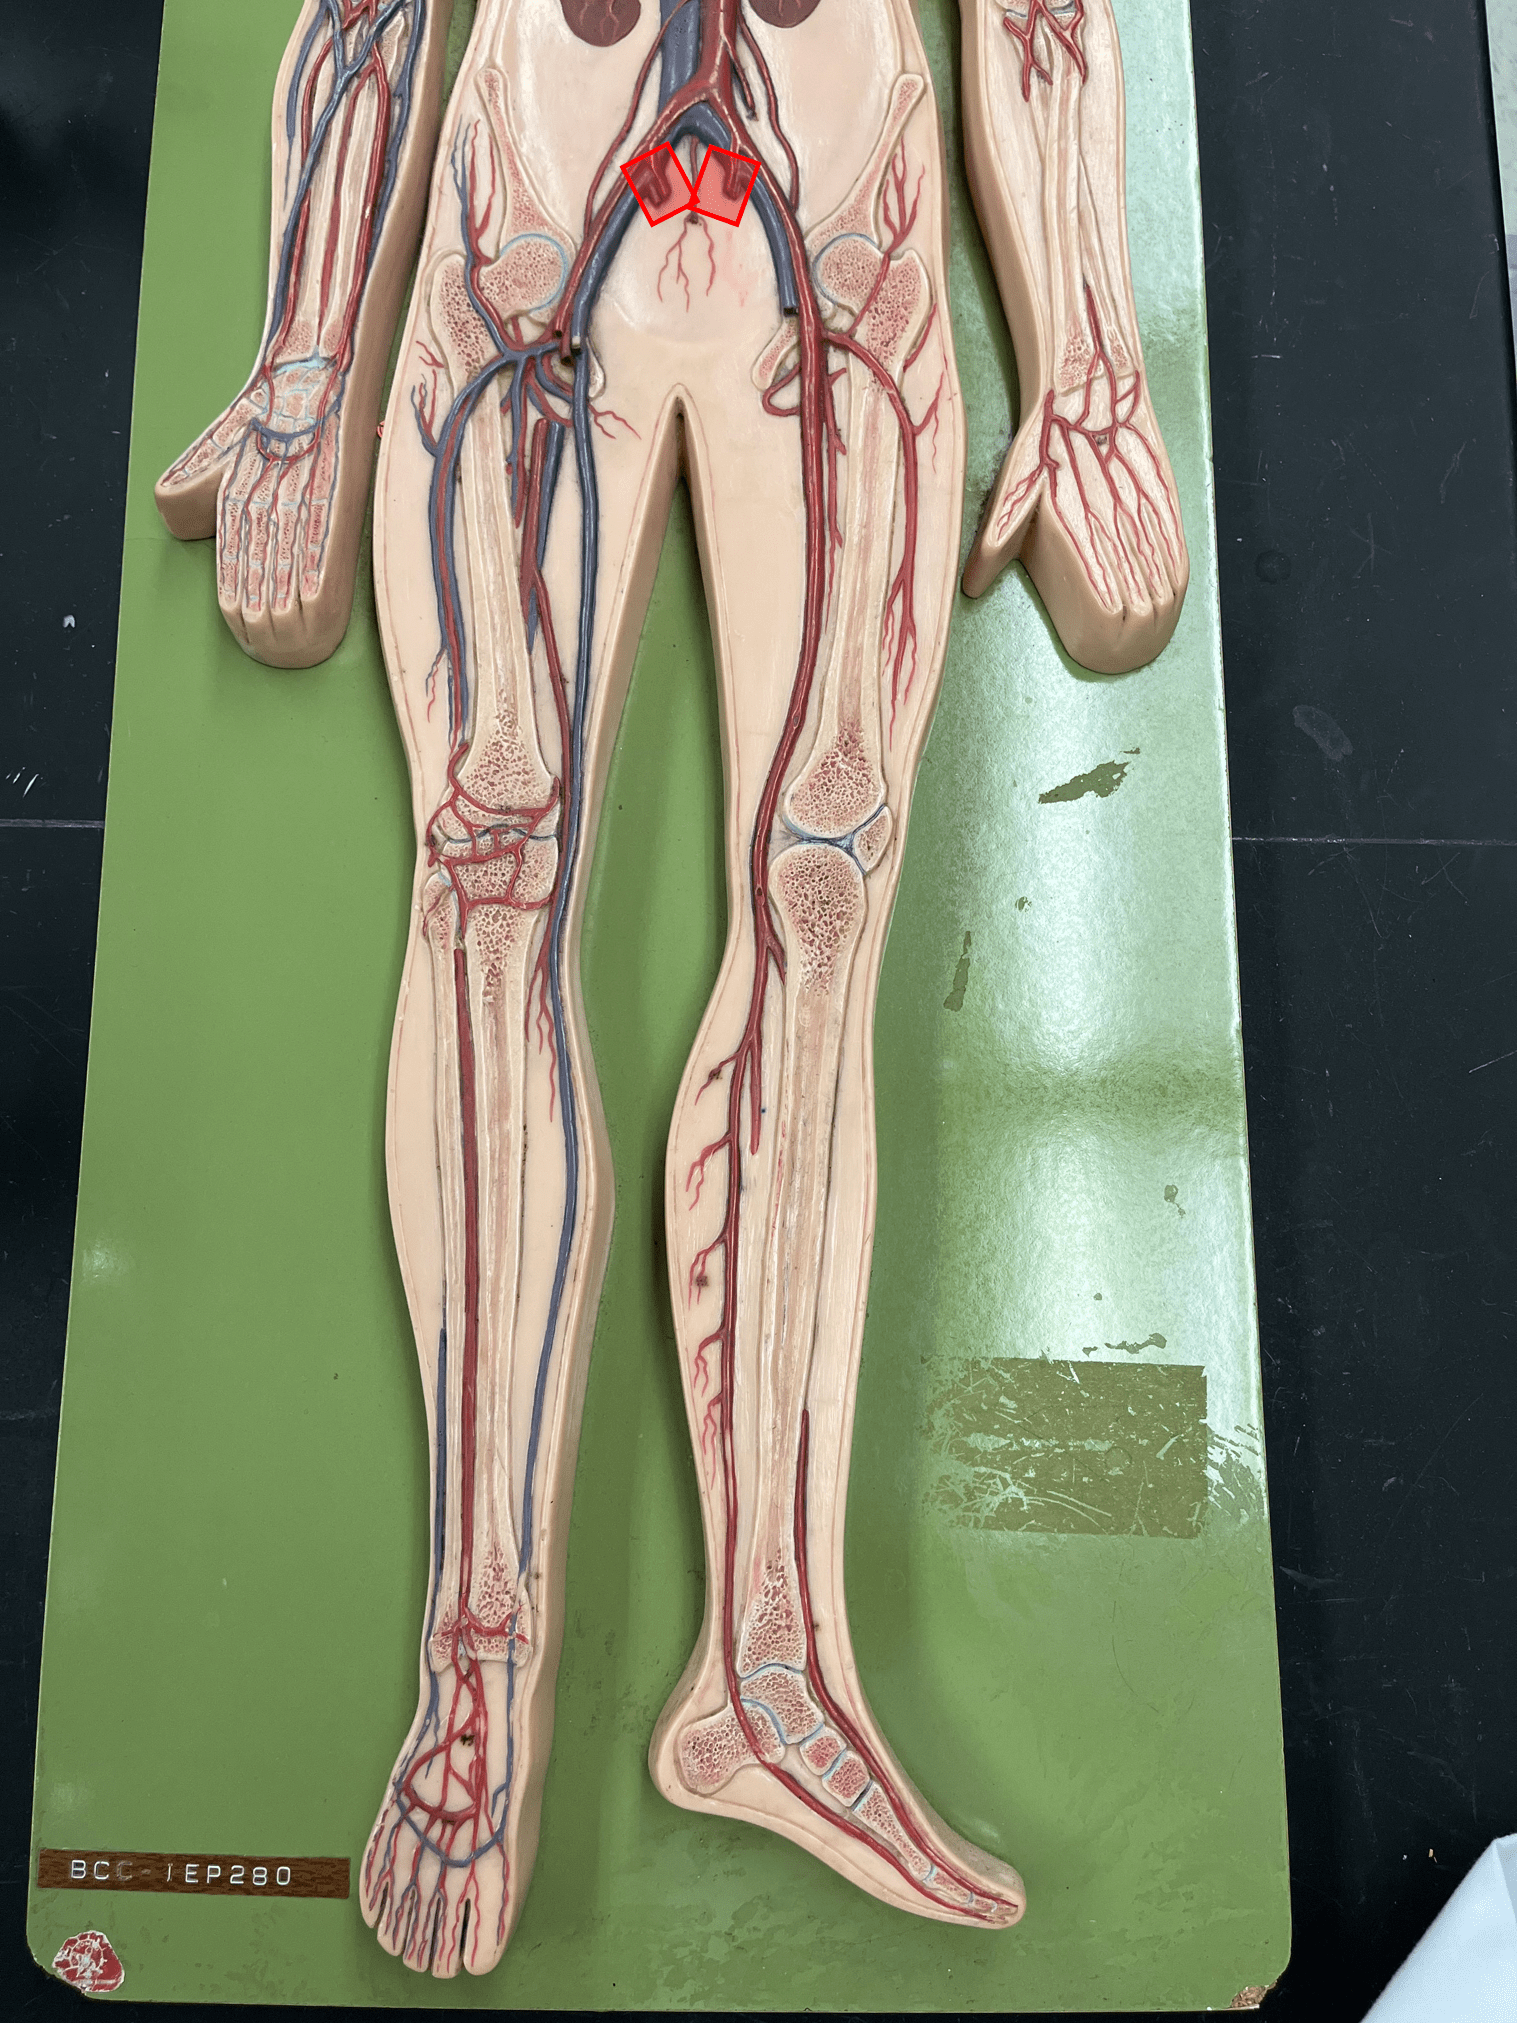

• Found between the tunica externa and tunica media.

11

New cards

• Originates from the brachiocephalic trunk (R.) or the aortic arch (L.).

• Supplies the head and neck through its branches.

• Originates from the brachiocephalic trunk (R.) or the aortic arch (L.).

• Supplies the head and neck through its branches.